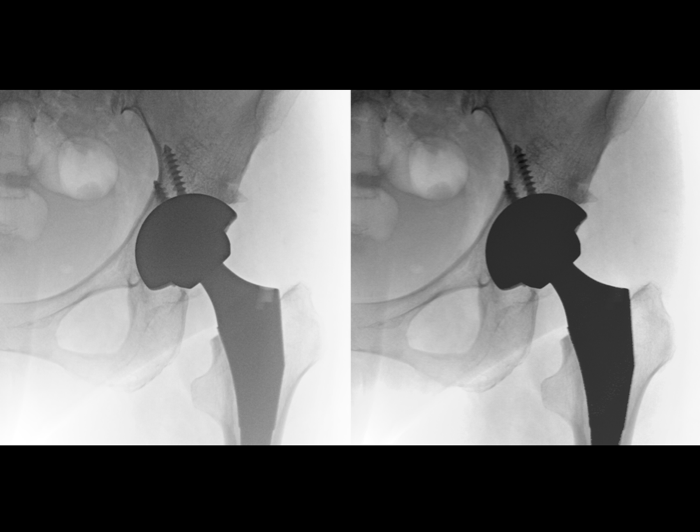

智能位置检测、金属检测和运动检测三大智能应用。智能识别患者拍摄位置,实时调节曝光参数,降低金属植入和运动干扰,成就低剂量高清影像。

临床应用

腰椎骨折后路复位椎弓根螺钉内固定术